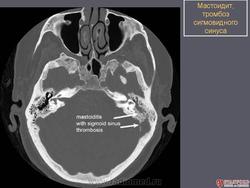

ЛОР. Височная кость. Заболевания сосцевидного отростка. +

Заболевания сосцевидного отростка.

Пневматизация сосцевидного отростка ( норма).